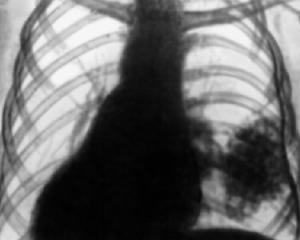

Диагностика плеврита

Диагноз ставится на основании:

- жалоб человека;

- данных осмотра, простукивания грудной клетки и выслушивания легких;

- рентгенографии органов грудной клетки;

- КТ грудной полости – при небольших и осумкованных (то есть ограниченных оболочкой) выпотных плевритах;

- УЗИ легких.